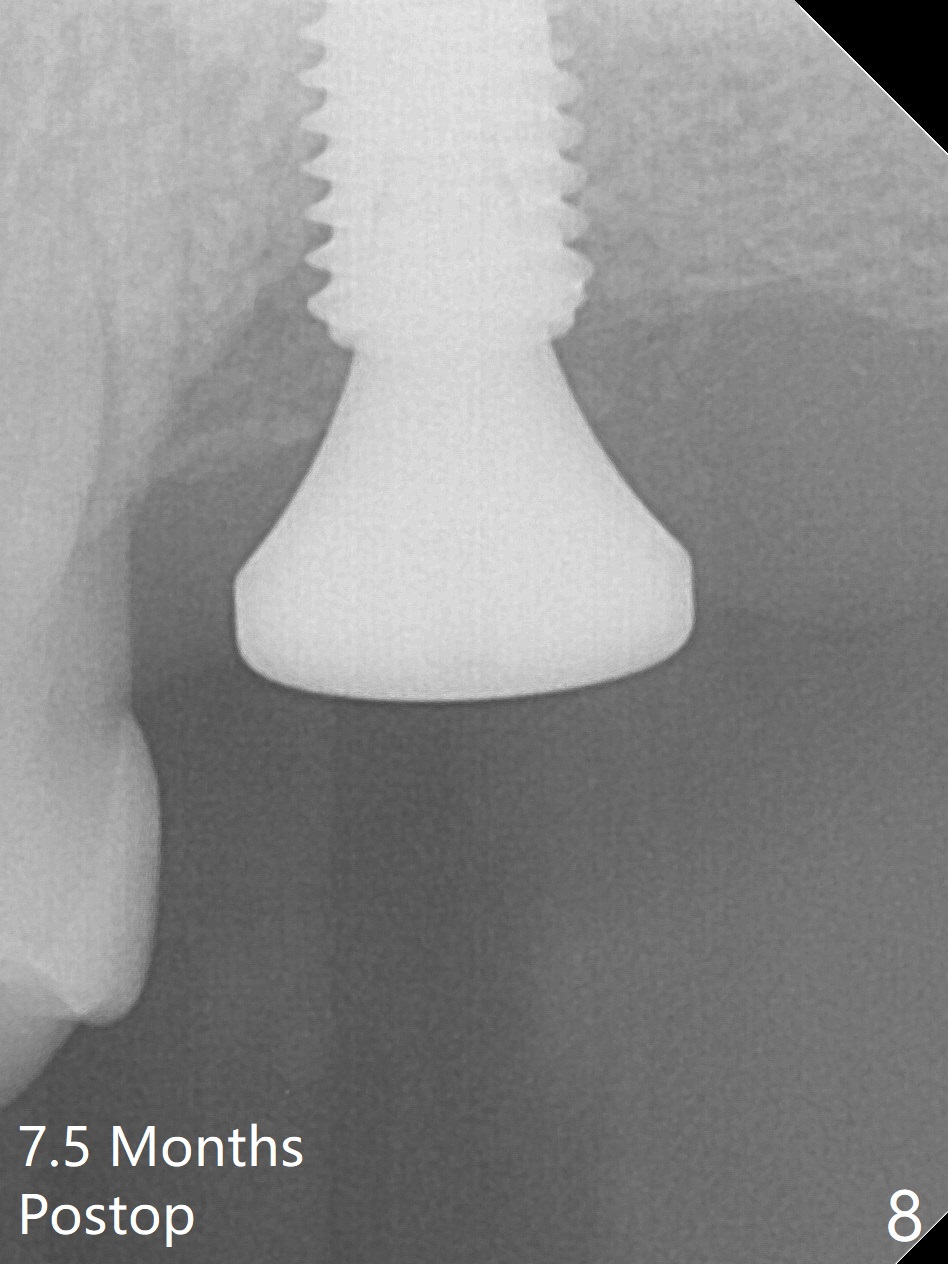

Although the buccal (Fig.1 (mesial view of the extracted tooth #15): B) root is larger than the palatal (P) one, the palatal socket is larger than the buccal one (Fig.2 white area) because of the bone loss of the former. For better restoration, osteotomy (Fig.2 red line) is initiated in the buccal slope of the septum (S) so that the final osteotomy is in the middle of the whole socket (Fig.3 red box). In fact a 3 mm stopper is not used because of the slope and the clumsy stopper. Stopper would be indicated if the bottom of the bone were flat. At first a 4x10 mm dummy implant is placed with stability (Fig.4). After further osteotomy and sinus lift (Fig.6 red dashed line: sinus floor), a 5x10 mm implant is placed with 30 Ncm, followed by insertion of a 5.2x8(2) mm temporary abutment (Fig.5,6). The latter holds an immediate provisional and Vanilla Graft/Osteogen (Fig.7 *) in place (^: distal crestal bone). Although the bone looks normal around the implant 7.5 months postop (Fig.4), the implant is unstable, probably due to the large preexisting defect. In contrast the implant placed at the healed site of #3 is stable 6.5 months postop. The 8x5 mm healing abutment that dislodged for 1 day could not return. A 6x5 mm one is used; it appears that the bone density mesial and distal to the implant is low (Fig.9 *). The implant looks normal and is stable 13 months postop (Fig.10). A 5.7x5.5(5) mm cementation abutment is placed for a provisional (progressive loading, Fig.11). There is no pain associated with the provisional for mastication. Impression is taken 7 days later. The patient has pain when the permanent crown is cemented. It appears that the implant does not osteointegrate and should be removed. A 6x14 mm tissue-level implant will be immediately placed following a 5 and 6x14 mm taps and bone graft and PRF (Metronidazole). In fact there is no pain when the existing abutment is torqued at 35 Ncm 1 year 8 months postop (Fig.12). The mesiogingival portion of final restoration (Fig.13 arrowheads) should be bulky so that the gingival embrasure (red dashed line) is minimal to reduce food impaction.